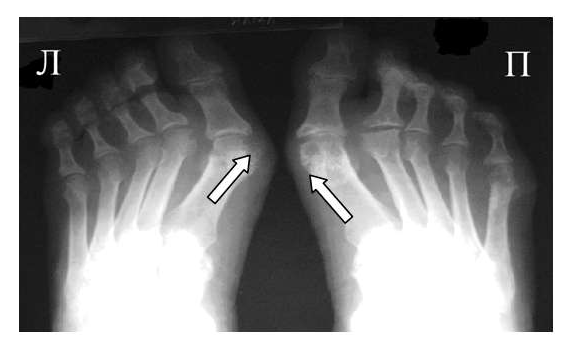

Рис. 2 Симптом «пробойника» в головках плюсневых костей обеих стоп в сочетании с вальгусной девиацией I плюсне-фаланговых суставов

Эрозии часто обнаруживаются в верхней и медиальной части плюсневой головки и часто в сочетании с вальгусной девиацией суставов. Типичным является асимметричность изменений (рис. 2).